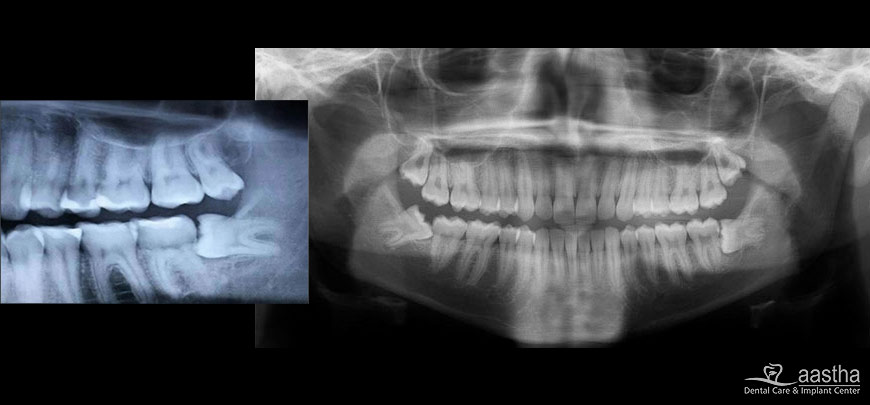

OPG X-ray is advised to check the presence and alignment of the wisdom tooth in relation to the adjoining bone and nerves. Both medical and dental histories are taken to avoid any complications.